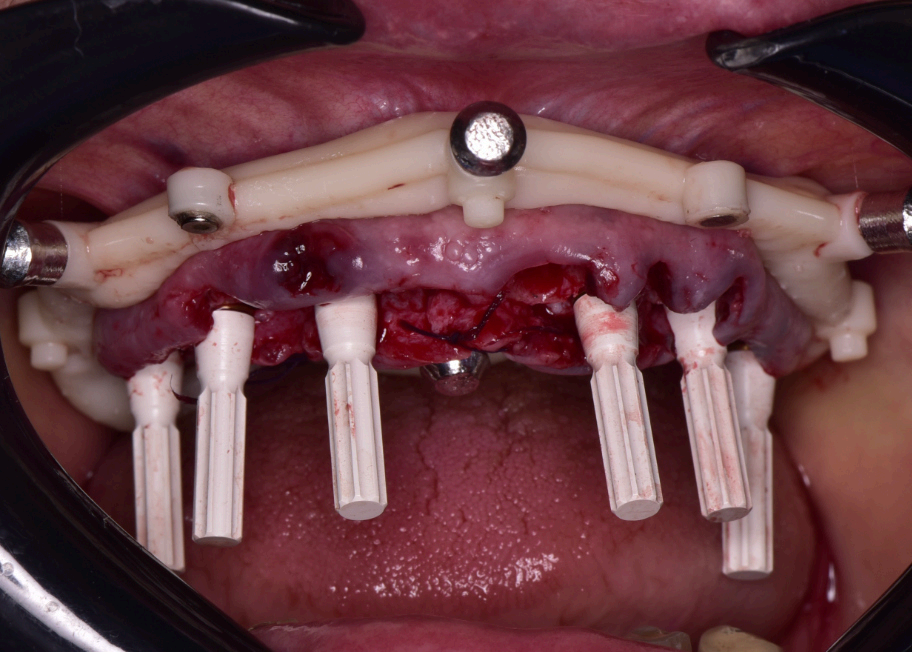

Group 2: Surgical Procedure Fig. 2.1: 3D model of the stackable surgical guide with fxation bar. Fig. 2.2: Occlusal view of the osteotomy guide in use during surgery. Fig. 2.3: Frontal intraoral view post-implant placement with MUAs attached. Fig. 2.4: Occlusal view of coded scan body captured by Shining3D Elite photogrammetry.

The surgical procedure was performed under local anesthesia in a single session. The residual roots at 13 and 21, along with the fractured teeth at 22 and 13, were extracted with minimal trauma to preserve the surrounding bone and soft tissue. The stackable guide was secured intraorally using the fxation bar anchored to the maxilla, providing a stable reference for implant placement (Fig. 2.2). Osteotomies were prepared at the planned sites (16, 14, 12, 22, 24, 26) using the guide’s drilling sleeves, ensuring accuracy in depth and angulation. Six implants were inserted, and multi-unit abutments (MUAs) were immediately placed to facilitate prosthetic connection (Fig. 2.3).

Following implant placement, intraoral photogrammetry was performed using the Shining3D Elite scanner. Scan markers were attached to the MUAs, and their positions were captured with high precision (Fig. 2.4, 3.4). Multiple scans were acquired, including the maxillary arch (Fig. 3.1), the fxation bar from the stackable guide (Fig. 3.2), the MUAs (Fig. 3.3), and the surrounding soft tissues (Fig. 3.5). The photogrammetry data was merged with conventional intraoral scans, using the fxation bar as a fduciary to align all datasets accurately (Fig. 3.7). A heat map generated in the software confrmed the precision of this alignment, with minimal discrepancies across the arch (Fig. 3.7). The scan markers were then converted to implant-specifc analogs compatible with the chosen implant system (Fig. 3.6).